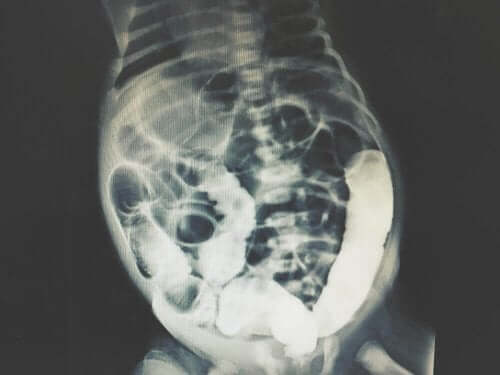

Röntgen av peritoneal dialys.